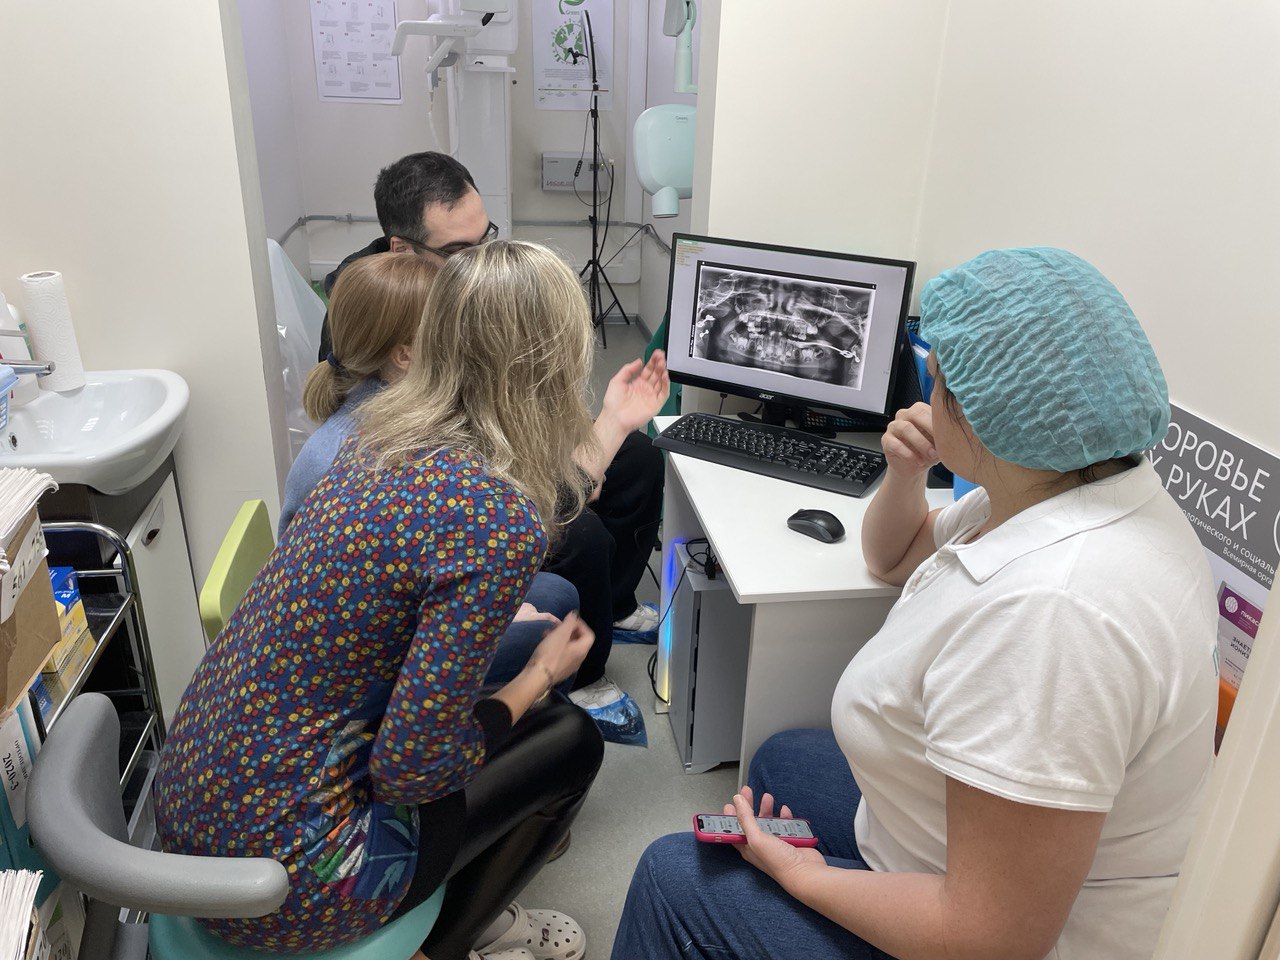

Компьютерная томография зубов (КТ зубов)

Компьютерная томография зубов - метод стоматологической диагностики, который показывает состояние зубов, корней, челюстной кости и мягких тканей во всех плоскостях.

КТ зубов представляет собой 3D изображение, которое отображается в специальной программе на мониторе компьютера и позволяет рассмотреть состояние челюсти со всех сторон и не упустить ни одной детали.

Зубная диагностика при помощи КТ является абсолютной альтернативой любому другому снимку зубов.

Важно! Выполнение компьютерной томографии зубов необходимо далеко не всегда. В некоторых случаях можно обойтись, например, прицельным снимком. Но, при составлении плана лечения в хирургической стоматологии, ортодонтии и т.д. КТ является обязательным, дабы не допустить ошибок в лечении.

КТ зубов представляет собой 3D изображение, которое отображается в специальной программе на мониторе компьютера и позволяет рассмотреть состояние челюсти со всех сторон и не упустить ни одной детали.

Зубная диагностика при помощи КТ является абсолютной альтернативой любому другому снимку зубов.

Важно! Выполнение компьютерной томографии зубов необходимо далеко не всегда. В некоторых случаях можно обойтись, например, прицельным снимком. Но, при составлении плана лечения в хирургической стоматологии, ортодонтии и т.д. КТ является обязательным, дабы не допустить ошибок в лечении.

Как проходит компьютерная томография

1

Перед началом манипуляции необходимо снять все металлические украшения

2

Далее подбородок пациента фиксируется на специальной подставке

3

Кабина КТ аппарат начинает медленно вращаться, делая более 500 снимков всего за 30 секунд работы аппарата

4

Изображение в 3D формате передается в специальную программу

важно

Подготовка к компьютерной томографии челюсти не требуется, как и последующая реабилитация.

Что Вы получите в результате:

- Точную диагностику

- Четкий план лечения

- Уверенность в здоровье своих зубов

БУДЬТЕ УВЕРЕНЫ!

В ПрофиСтиль мы используем аппараты последнего поколения, которые обладают высокими показателями качества изображения и абсолютно безопасны как для взрослых, так и для детей!